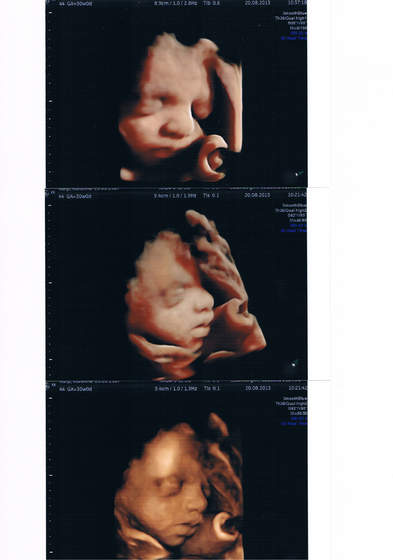

Chwalę się, że byłam dziś na tym darmowym usg- był mój lekarz, ordynator szpitala i dwóch panów od ustawiania sprzętu. Leżałam z głowicą na brzuchu z 35 minut, na dzień dobry ordynator poczęstował nas czekoladą nawet

Świetnie że się załapałam, bo nie wydałabym 200 zł na takie badanie, a tak to młody miał jeszcze dokładniej wszystko zmierzone i sprawdzone, bo ustawiali różne parametry usg, byłam krolikiem doświadczalnym

Pamiątka będzie cudowna, nie wiedziałam że aż tak dokładnie będzie widać Tomka- kurcze zapowiada sie, że będzie bardziej do M. podobny.